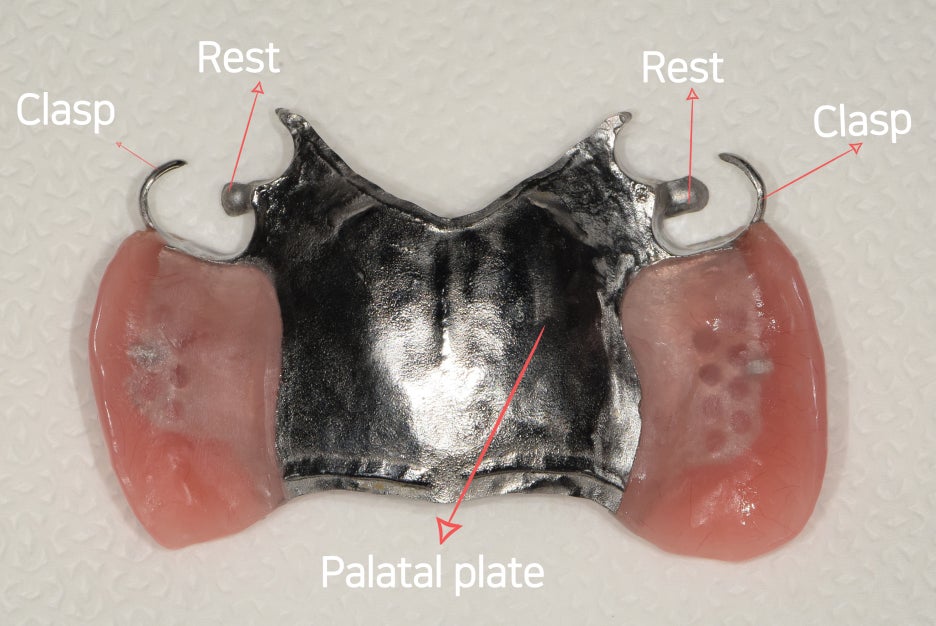

왜 그러냐면, 여러가지의 구조물들이

구강 내 환경에 맞게 설계가 되어야 되는건데

Rest, Clasp, ligual plate, palatal pate 라

불리우는 여러가지 구조물들이 한 몸이 되어서

기능 회복을 도와야 되기 때문입니다.

『부분틀니 구조』

사진에서 보실 수 있는거와 같이, 여러가지

구조물들이 서로 한 몸이 되어있는것을

볼 수 있죠?

최소 3가지의 구조물들이 엮여져야 되며,

서로가 가지고 있는 기능이 제 각기 다릅니다.

- Clasp : 고리 형태로 되어있으며, 서베이드 크라운에 걸려서 측방 교합력을 버티는데 도움을 줄 수 있습니다. 나아가, 흔들리지 않는 역할에 크게 기여 할 수 있으나 여기에 유지력과 고정력이 가장 많이 쏠리기 때문에 서베이드 크라운과의 적합도가 가장 좋아야 되는 곳 중에 하나입니다.

- Rest : 보통 Clasp 와 쌍을 이루는 구조입니다. 이는 수직 교합력을 버티는데 도움을 주며 맞물리는 대합치와 교합관계를 이룰 수 있습니다. 아래로 내려가거나 위로 올라가는 등의 위치 변화를 막는데 도움을 줄 수 있으며 이 또한 서베이드 크라운의 교합면에서 안착이 되어 제 기능을 발휘합니다.

- Palatal plate : 하악에서는 Lingual plate 로 설계되어야 됩니다. 이는 입 천장과 최대 접촉을 이루어야 되면서 음압을 유지할 수 있는 모양으로 설계가 되어야 좋은 결과를 얻을 수 있습니다. 그러면서, 금속으로 만들어지기 때문에 혹여 잘못 설계가 되었다면 입 천장을 누르는 등에 따라서 통증을 유발할 수 있겠습니다. 아울러, 조금 더 높은 유지력을 발생시키려 맨 뒤편에 있는 계단처럼 턱이 져 있는데 이는 soft tissue 와 hard tissue 의 경계면에 위치됩니다.